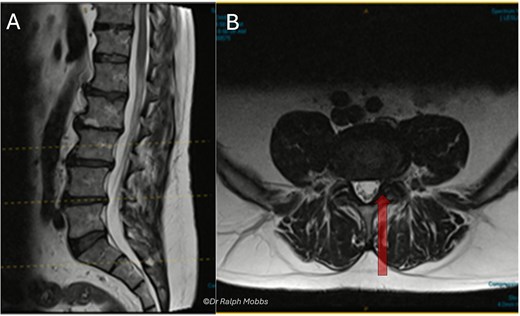

A 63-year-old male presented with persistent left-sided L5 radiculopathy that was refractory to conservative management. MRI revealed lateral recess stenosis at the L4–L5 level secondary to facet joint hypertrophy (Fig. 1).

Case 1 mid-sagittal (A) and axial (B) T2-weighted MRI at L4/5 with lateral recess stenosis (arrow).